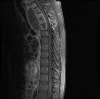

MRI : 염증 조직의 파급 정도를 알기 쉽습니다.

MRI : 척추 결핵(Spinal tuberculosis)

MRI : 척추 결핵(=Tuberculous spondylitis with large prevertebral abscess)